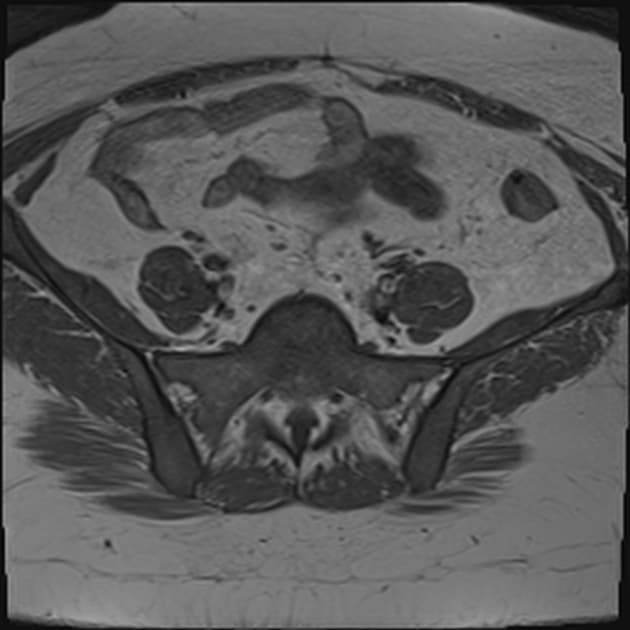

Cả hai buồng trứng đều to, nằm gần nhau, chạm vào nhau ở đường giữa, tạo thành "dấu hiệu buồng trứng hôn nhau (kissing ovaries sign)", bên trong chứa các tổn thương dạng nang hai bên với nội dung xuất huyết và các mức dịch - dịch (fluid-fluid levels), mô tả mẫu hình phân tầng (dấu hiệu shading sign) – phù hợp với lạc nội mạc buồng trứng hai bên (bilateral endometriomas).

Tử cung, cả hai buồng trứng và trực tràng bị kéo sát lại gần nhau do các dải dính co thắt / xơ hóa, dẫn đến "dấu hiệu lá cỏ ba lá (cloverleaf sign)" – một hình ảnh mới được mô tả trong lạc nội mạc tử cung xâm lấn sâu (deep infiltrating endometriosis).

Hình ảnh minh họa dấu hiệu lá cỏ ba lá (cloverleaf sign) khi tử cung, cả hai buồng trứng và trực tràng bị kéo sát lại gần nhau do các dính co thắt, cho thấy lạc nội mạc tử cung xâm lấn sâu (deep infiltrating endometriosis).